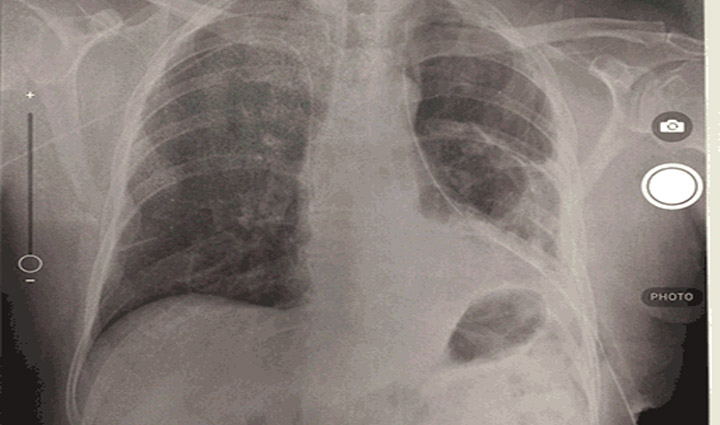

Mobile Chest X-Ray Analysis is an experimental project to showcase the offline Chest X-Ray model in Xamarin for Android and iOS. By leveraging AI technologies developed by the Microsoft Cloud AI Team we hope to increase the efficiency, accuracy, and speed with which radiologists can deliver diagnoses on 14 different chest conditions. In particular, our project can address the lack of radiologists available in developing countries by providing an alternate method of diagnosis for local doctors. Mobile Chest X-Ray Analysis showcases how developers can infuse AI into their own mobile applications.